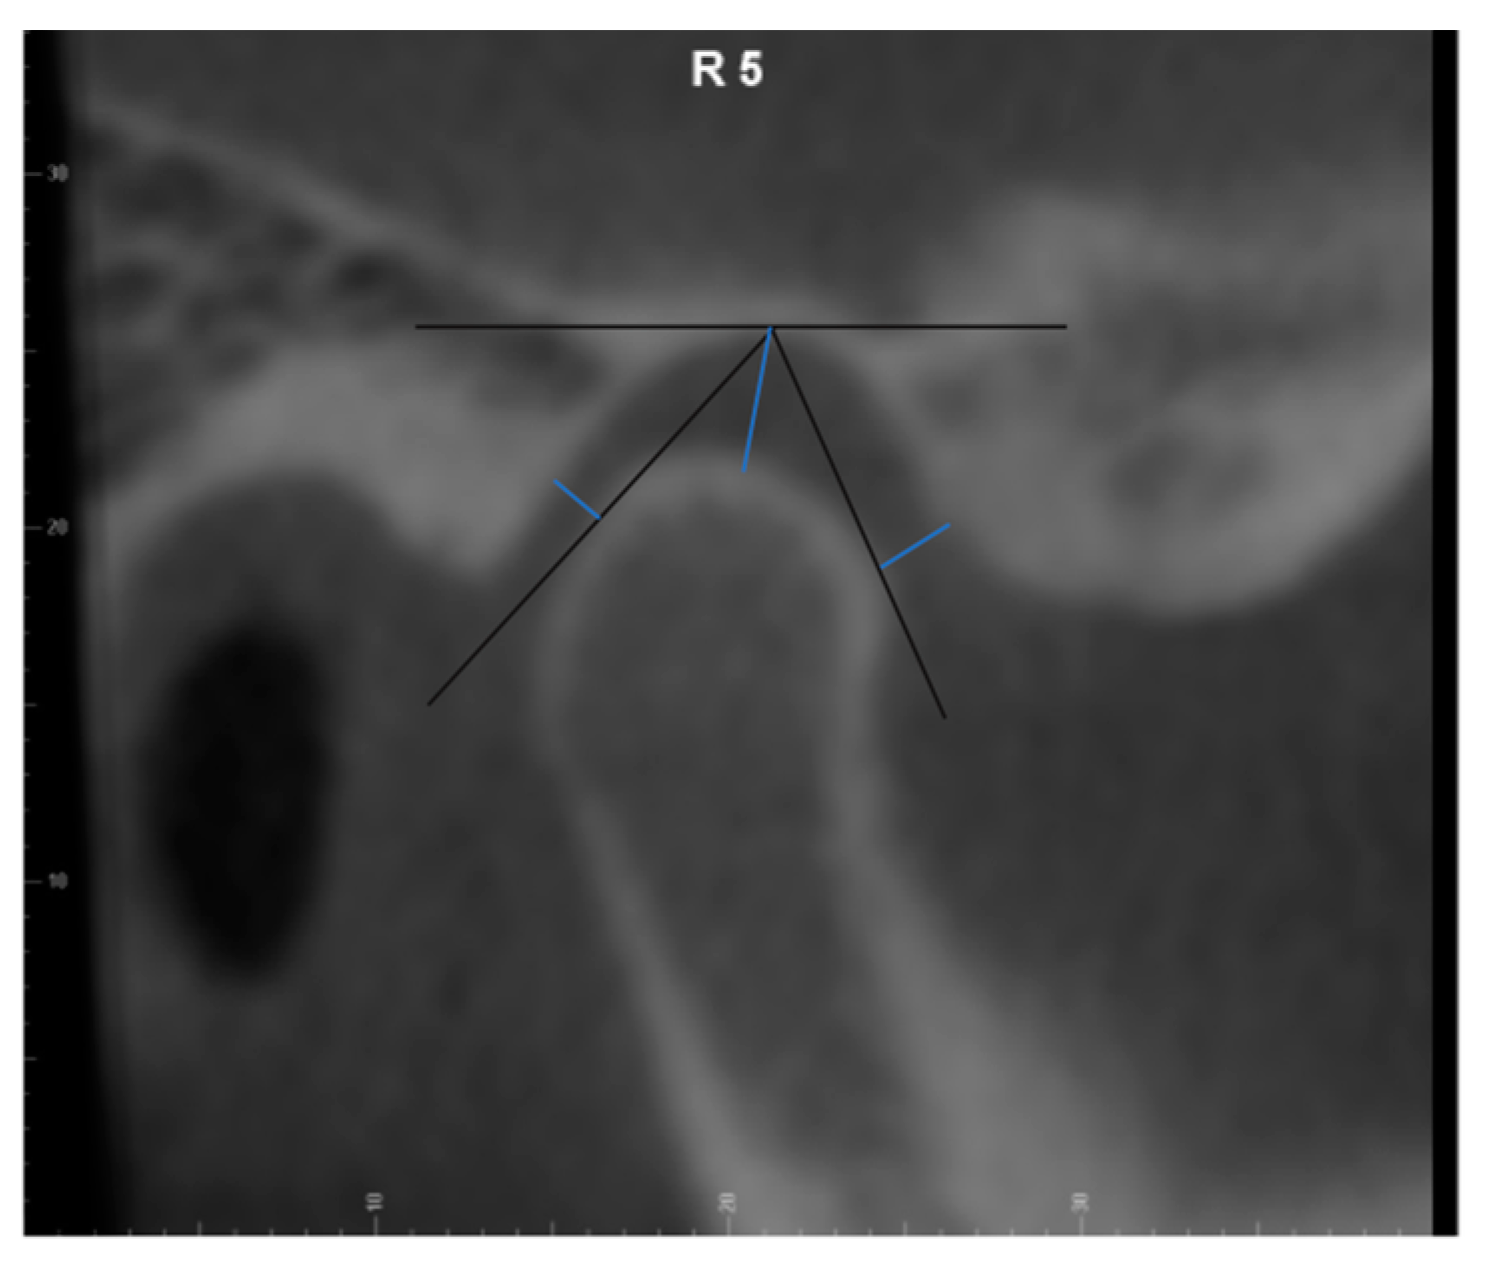

All CBCT images were oriented and analyzed using the Dolphin Imaging 3D software (version 11.9, Dolphin Imaging & Management Solutions, Chatsworth, CA, USA). Each head was oriented in three planes of space for frontal and lateral views. The head was oriented in the frontal view with the floor of both orbits parallel to the floor [16]. In the right-side lateral view, the head position was adjusted so that the glabella was used to define the distance from the facial axis point of the maxillary central incisor to the goal anterior limit line (GALL) line matched to the clinical record. The lateral borders of the orbital rim, ramus borders, and mandibular angles were superimposed to the best fit from left and right. After orientation, the axial image demonstrating the largest mediolateral dimension of the condyle was selected. Then, we drew the reference line connecting the medial and lateral poles of the condyle [17]. Nine sagittal TMJ slices were made with 2.0 mm thickness for each joint. The 3rd, 5th, and 7th cuts from the right TMJ were saved as the lateral, central, and medial pole and the 3rd, 5th, and 7th cuts from the left TMJ were saved as the medial, central pole, and lateral pole, respectively (Figure 1). Three linear measurements of TMJ space, including the anterior joint space (AS), superior joint space (SS), and posterior joint space (PS), were performed on each cut as previously described [13]. Briefly, the distance from the most superior point of the condyle to the most superior aspect of the glenoid fossa was measured as the superior joint space (SS). Lines tangent to the most anterior and posterior aspects of the condyle were drawn from the most superior aspect of the glenoid fossa. The shortest distances from the anterior and posterior tangent points to the glenoid fossa were measured as the anterior joint space (AS) and posterior joint space (PS) (Figure 2).

Figure 2. Temporomandibular joint space measurement.